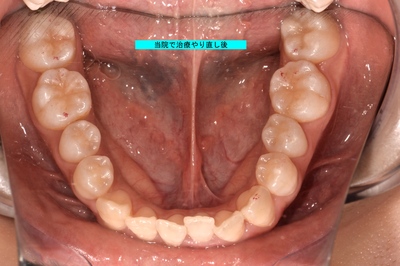

術後

充填部位はほぼ判別不可能。

虫歯の深かったった部位は、神経を保護、第2象牙質生成確認のため経過観察後再治療予定だが、矯正治療もご希望のため、矯正治療終了後ホワイトニング等行った上で再治療予定。

治療時間約60分。